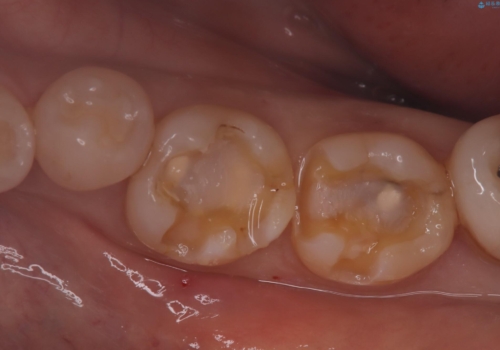

- 主訴:詰め物が外れた これを機に白い詰め物にやり替えたい

左下7番目の歯の詰め物が外れ、セラミックインレーでのやり替えとなりました。

隣在歯にも保険適用もメタルインレーが入っており、咬合面のインレーと歯質の境目が虫歯になっていたこともあり、合わせてのやり替えとなりました。

左下7番めの歯、フロスを通したらインレーが外れてしまったとのことで、適合具合の精密さや、これを機に白い詰め物にしたいとのことからセラミックインレーでのやり替えとなりました。

また、6番目の歯にも保険適用のメタルインレーが入っており、咬合面インレーと歯質境目にう蝕を認め合わせてのやり替えとなりました。